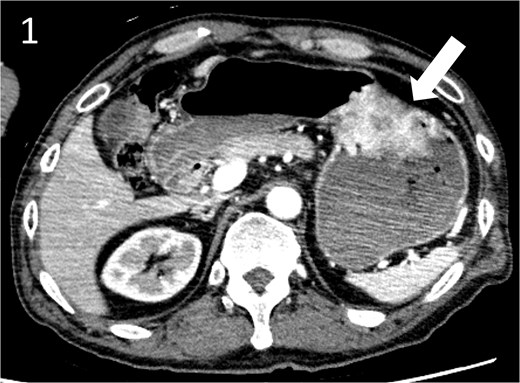

A 59-year-old man presented to the emergency department with loss of consciousness and hematemesis. His blood pressure was 90/50 mmHg. The patient’s haemoglobin level was 7.9 g/dL. The patient was haemodynamically unstable, and 12 units of red blood cell (RBC) concentrate were administered. Contrast-enhanced computed tomography (CT) revealed a gastric hyper-vascular mass on the lesser curvature (Fig. 1). Emergency upper gastrointestinal (GI) endoscopy performed under endotracheal intubation and ventilatory management revealed a large type 1 oozing tumour (Fig. 2a). Haemostatic procedures were not performed due to technical difficulties. Emergency angiography revealed a tumour stain from the left gastric artery, which was coil embolized (Fig. 3). Upper GI endoscopy 2 days later revealed no bleeding (Fig. 2b). After embolization, the patient became haemodynamically stable. It was later discovered that he had undergone open omental filling at another hospital 1 year prior due to GC perforation and left his disease untreated for a year at his own discretion. The patient received combination chemotherapy with S-1 and oxaliplatin, which was remarkably effective. Eight months after embolization, laparoscopic total gastrectomy with Roux-en-Y reconstruction and lymph node dissection were performed. The final histopathological diagnosis was T2N0M0 stage IB. Macroscopic findings revealed a type 1 tumour in the upper part of the stomach. Histopathological findings revealed that the tumour was a well-differentiated tubular adenocarcinoma. All surgical margins were negative. The patient had an uneventful postoperative course and was discharged 7 days after surgery. The patient was well, with no recurrence noted during the 35 months of follow-up.

Contrast-enhanced computed tomography image showing a gastric hyper vascular mass on the lesser curvature (arrow).